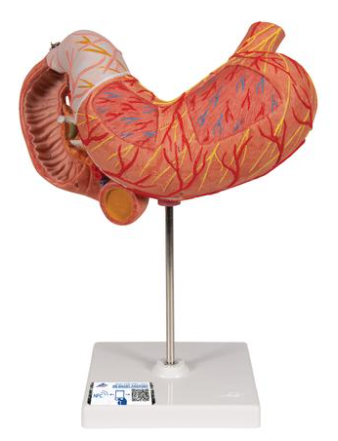

Anatomy

Anatomical models and charts by Body System or Anatomical Region for Nursing, Physical Therapy, and Medical Education.